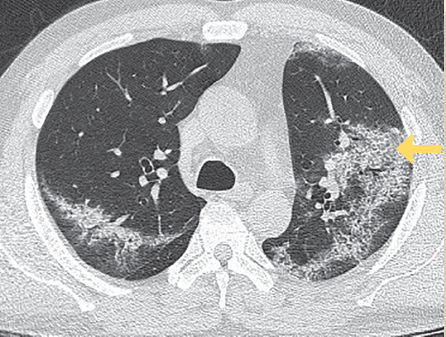

Estadio 2: De 5 a 8 días. Se observó un patrón en empedrado en el 53% de los pacientes. En este estadio la infección rápidamente se agrava y se extiende de forma bilateral, multilobar con patrón difuso en vidrio despulido, en empedrado o patrón de consolidación (figura 3).